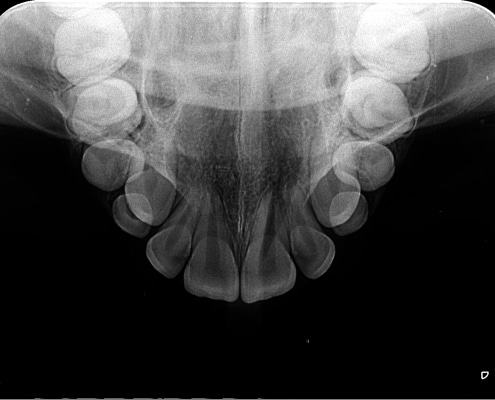

RADIOGRAFIA OCLUSAL